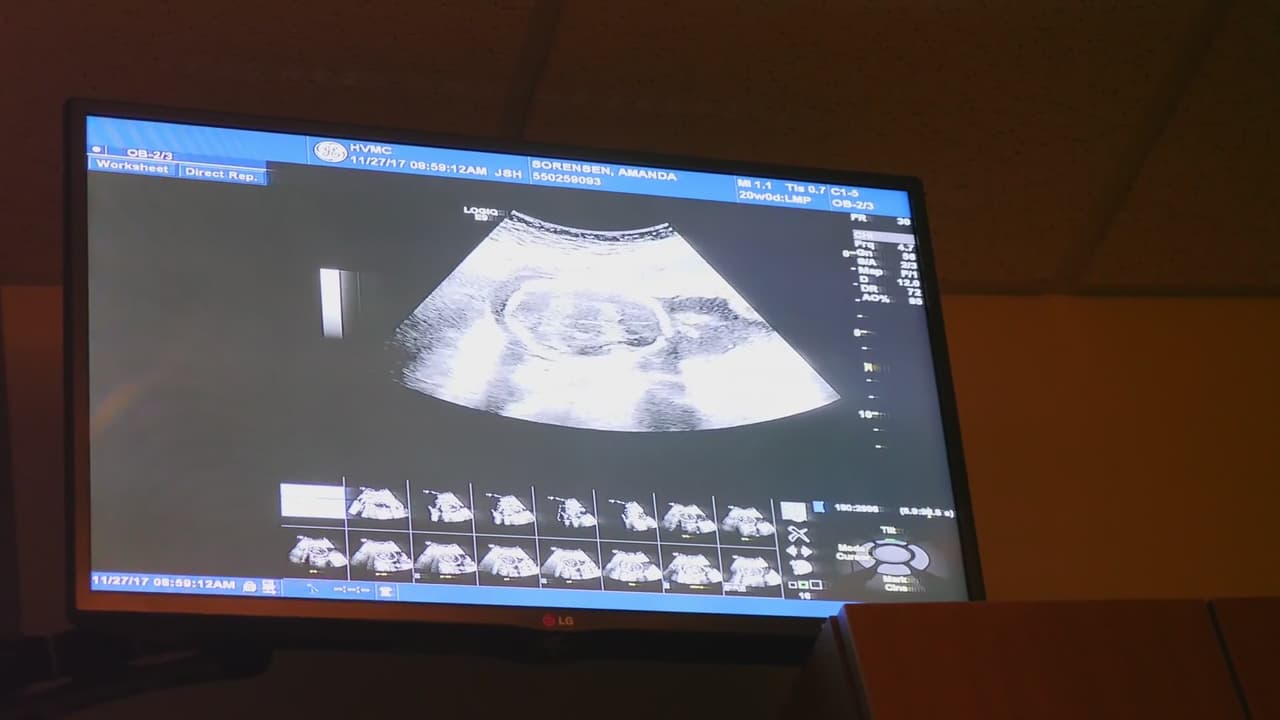

Georgia ocupa el puesto 37 en la tasa de mortalidad infantil. Una alerta para las futuras madres es que sepan reconocer las señales de advertencia y los derechos que tienen en el estado.